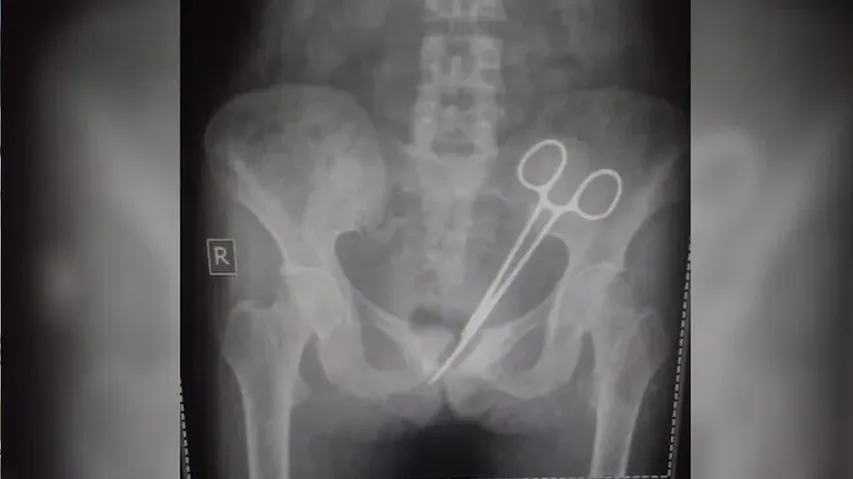

ସର୍ଜରୀ ବେଳେ ଡାକ୍ତର ଛାଡ଼ିଥିଲେ କଇଁଚି, ୧୨ ବର୍ଷ ପରେ ମହିଳାଙ୍କ ତଳି ପେଟରୁ ବାହାରିଲା